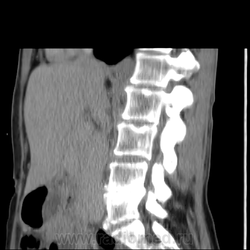

Обнаружилось небольшое образование низкой плотности, с достаточно ровными, четкими контурами парааортально справа около ножки диафрагмы на уровне тела L1 позвонка.

При нативе плотность 6HU, паренхиматозная - 18-20HU, экскреторная (15 минут) - 60-65HU.

Выкладываю по очереди срезы на одинаковых уровнях, сначала паренхиматозная, потом отсроченная фазы.